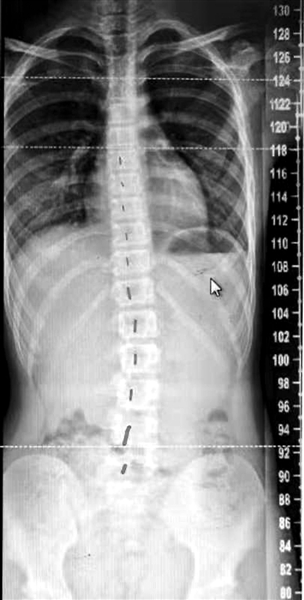

“12岁女孩脊柱明显侧弯旋转,没有支具或手术指征,经过合理康复锻炼后,恢复得很好……”日前,宁波市第一医院脊柱外科夏冬冬医生在朋友圈晒图,分享一位脊柱侧弯患儿的康复经历。夏冬冬告诉记者,早先他和同事在宁波某小学筛查发现,每10个孩子中就有2个疑似脊柱侧弯的孩子。骨科专家提醒广大家长,要及时发现孩子的脊柱问题,避免需要手术干预的严重后果。

家长把女儿带到市第一医院请夏冬冬进行诊治,拍片检查后发现,女孩果然有脊柱侧弯,她的脊柱呈螺旋状旋转,所幸发现得早,侧弯的度数在10度左右。虽然只是轻度的侧弯,还达不到戴支具矫正或手术的程度,但如果不加干预,侧弯会继续发展。

女孩在医生的指导下进行了康复锻炼,每天半个小时做规定的锻炼动作。三个月以后,女孩再来医院复查,有了喜人的效果,影像片上,她曾经侧弯10度的脊柱变成了一根直线,恢复得非常好。